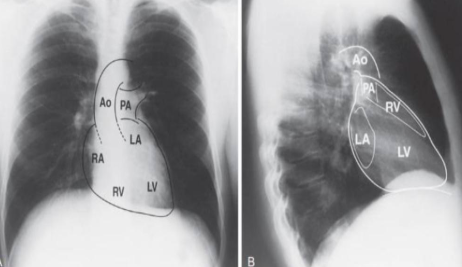

what is this?

posteroanterior chest radiograph. B.lateral chest radiograph